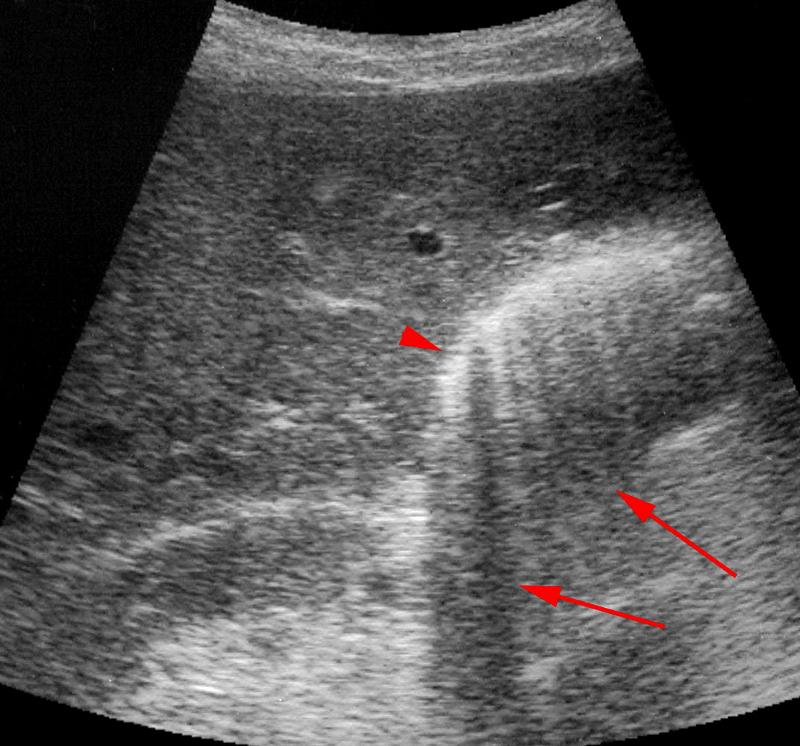

Emphysematous Cholecystitis

Gas forming bacteria in gallbladder wall yields to high intensity echoes and comet tail artifact